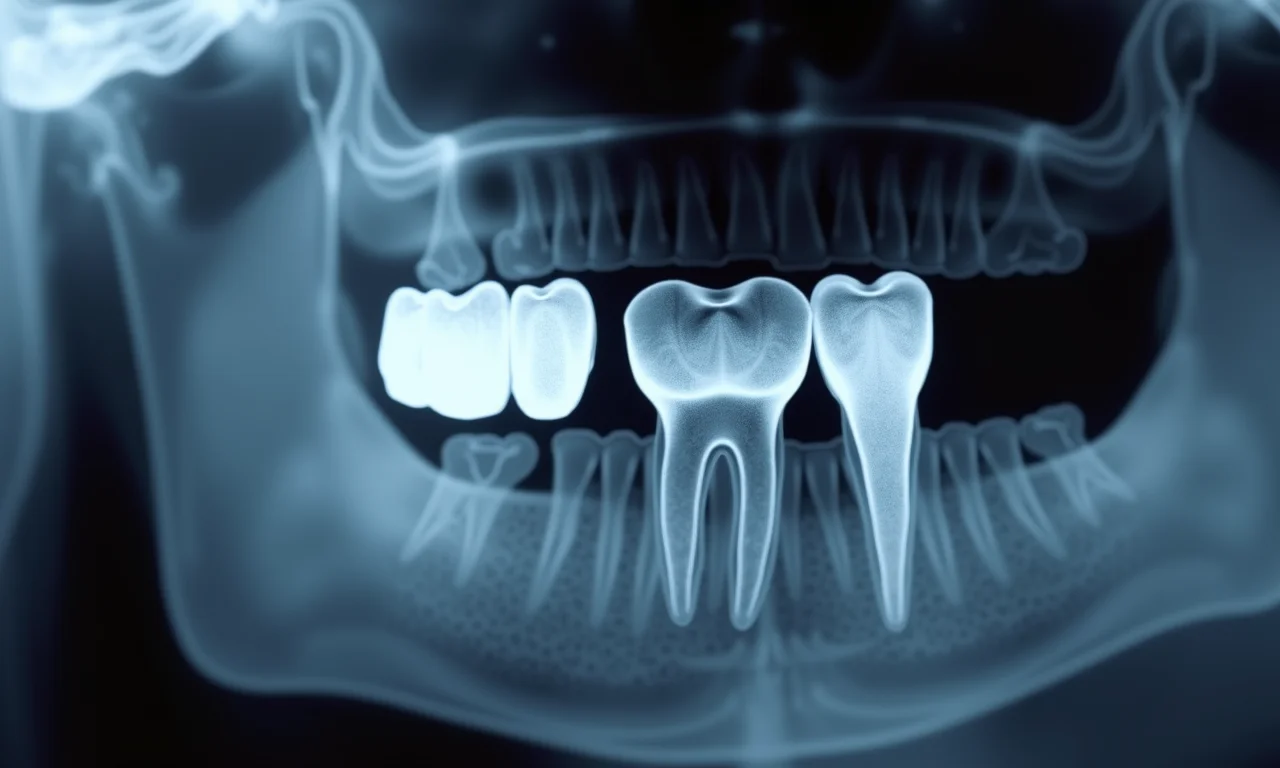

A extração dos dentes do siso é um procedimento cirúrgico realizado por um dentista ou cirurgião bucomaxilofacial. Antes da cirurgia, é feita uma avaliação clínica e radiográfica para planejar o procedimento e identificar possíveis complicações. Durante a cirurgia, é aplicada anestesia local para garantir o conforto do paciente. Em alguns casos, pode ser utilizada sedação para pacientes mais ansiosos.